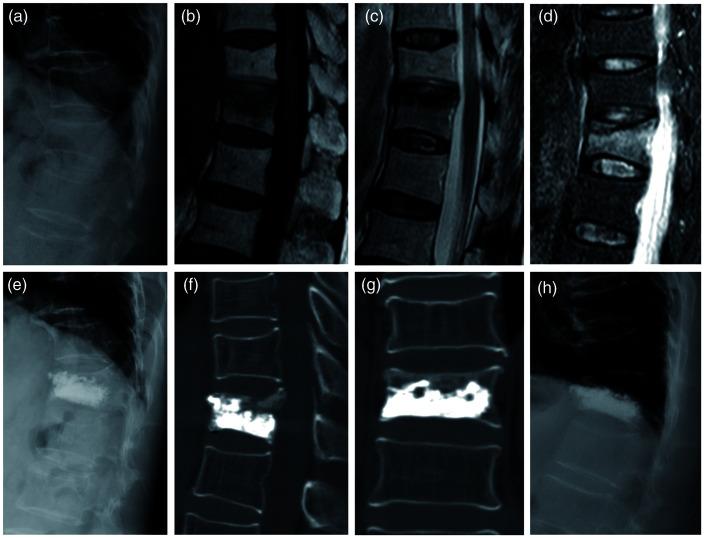

This retrospective matched-cohort study included patients 50-90 years of age who had undergone PVP for single level vertebral compression fractures (VCFs) from February 2015 to December 2018. Insufficient (Group A)/sufficient (Group B) distribution of bone cement in the fracture area was assessed from pre- and post-operative computed tomography (CT) images. Assessments were before, 3-days post-procedure, and at the last follow-up visit (≥12 months).

Of the 270 eligible patients, there were 54 matched pairs. On post-operative day 3 and at the last follow-up visit, significantly greater visual analogue scale (VAS) pain scores and Oswestry Disability Index (ODI) scores were obtained in Group B over Group A, while kyphotic angles (KAs) and vertebral height (VH) loss were significantly larger in Group A compared with Group B. Incidence of asymptomatic cement leakage and re-collapse of cemented vertebrae were also greater in Group A compared with Group B.

Insufficient cement distribution may relate to less pain relief and result in progressive vertebral collapse and kyphotic deformity post-PVP.